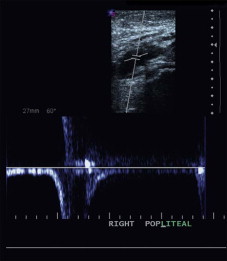

The small saphenous vein (SSV) is examined for dilation and reflux with the patient standing and facing away from the technologist and the popliteal vein is imaged from this approach as well. Examination of the SSV is started at the ankle posterior to the lateral malleolus. The course of the vein is traced proximally where it very quickly drifts to the midline of the calf and can clearly be identified within its superficial fascial compartment. Branches and connections are usually seen in the mid-calf and the operator eventually traces these branches but not until the entire course of the SSV is studied.

The examination is done in the transverse view until the whole course of the vein is mapped. Often the vein will extend proximally past the popliteal fossa and sometimes eventually connects to the GSV in the upper medial thigh or groin as the so-called vein of Giacomini. The SSV is also interrogated in the longitudinal view near the popliteal fossa to document the saphenopopliteal junction. This is a critical step since the SSV may empty into a gastrocnemius branch, which then enters the popliteal fossa. If this is not well understood and observed by the surgeon, important errors can occur and precipitate damage and/or thrombosis of the deep venous system at the time of ablative treatments. The small diameter of the SSV may make it difficult to interrogate with pulsed Doppler or color flow in longitudinal orientation and occasionally this must be performed in transverse orientation.

Small saphenous vein (SSV) stripping is performed less often and when it is performed, it may be limited to a segment and not the entire SSV. The superior termination of the SSV is variable ( Fig. 10.8 ) and must be clearly delineated at the time of any diagnostic imaging study to provide sufficient information on which therapeutic decisions may be based. It may be useful to re-image the patient just before surgery and to mark the location of the SSV and its termination at and above the knee to allow accurate placement of incisions. This may even be performed in the operating room with the patient prone on the operating table. SSV segments at least 4 mm in diameter with demonstrable reflux can be considered for stripping. It is rarely necessary to remove the distal third of this vein, and normally the vein can be removed to the proximal or mid-calf just below the last major communicating varicosity identified during the duplex examination.